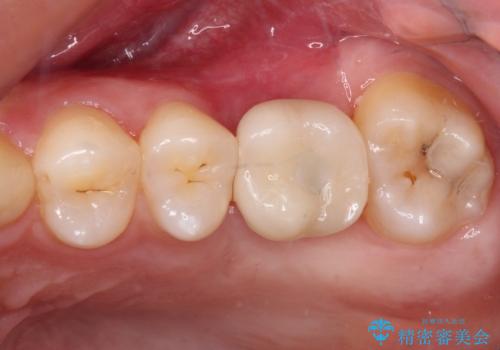

奥歯の虫歯は抜歯が必要であったので、矯正治療前に抜歯をし、矯正治療と並行してインプラントによる補綴治療を行うこととしました。

当院の特徴は、矯正治療とインプラント補綴治療の担当医が同じ歯科医師であるため、両方の治療を並行して行うことができます。